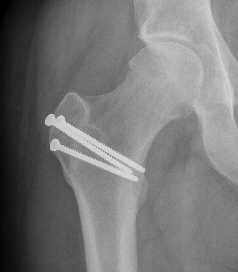

X-ray

Soft tissue swelling

Arthritic changes

Bone destruction

- invasion of adjacent metaphyseal cancellous bone

- may be suggestive of neoplasm

Bony involvement PVNS

Hip PVNS

Hip PVNS with erosions